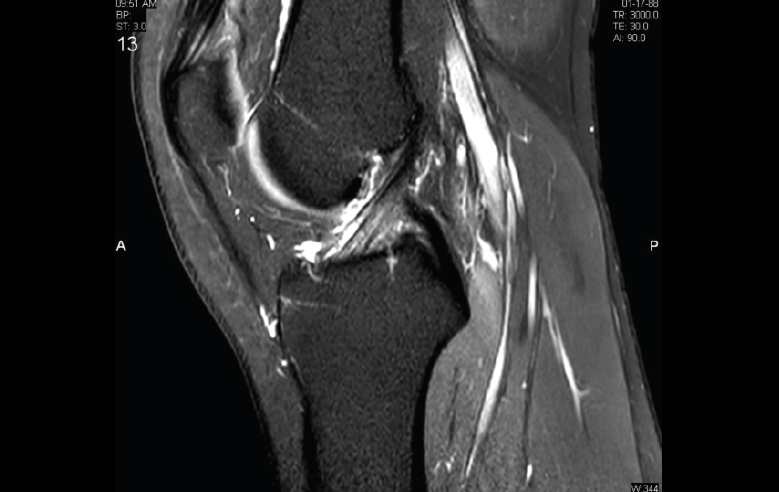

4. Lesiones isquémicas

4.1. Necrosis avascular (NAV)

En la NAV (aséptica, isquémica u osteonecrosis), hay una pérdida del flujo de sangre en el tejido óseo que hace que el hueso muera.

Se produce por un trastorno de la irrigación sanguínea o por lesiones celulares en el hueso y en la médula ósea.

Puede observarse en la RM la disminución de la intensidad de la lesión mucho antes de que se aprecie con otras pruebas diagnósticas (Figura 51).

Figura 51. Corte de secuencia T2 Fat-Sat coronal: lesión osteocondral con necrosis avascular del fragmento óseo.

4.2. Infartos

Los infartos medulares óseos aparecen en el 0,06% de los pacientes a quienes se les ha realizado una RM del aparato locomotor. Se presentan como lesiones segmentarias, puramente medulares, sin afección cortical, normalmente múltiples y que afectan predominantemente a los huesos largos de las extremidades, sobre todo las inferiores. La RM es esencial en el diagnóstico por imagen, apareciendo como lesiones óseas intramedulares de contornos serpiginosos hipo- o isointensos en secuencias T1 e hiperintensos en T2. Por tanto, la RM es el instrumento crucial en las fases iniciales, ya que permite caracterizar las lesiones y proceder a su diagnóstico temprano(19)(Figura 52).

Figura 52. A: corte de secuencia coronal T2 Fat-Sat con infartos óseos en el fémur y la tibia; B: corte de secuencia sagital T1 con infartos óseos en el fémur y la tibia.